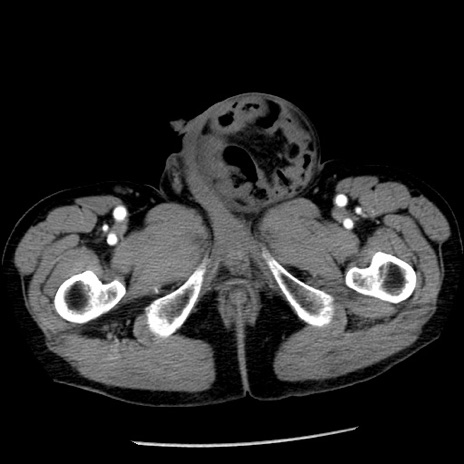

症例26(横断像)

【症例】80歳代男性

【主訴】嘔吐

【現病歴】昨晩2回嘔吐あり、今朝になっても嘔吐あり。来院。

【既往歴】胃潰瘍

【身体所見】意識清明、BT 37.6℃、BP 166/95mmHg、HR 100bpm、SpO2 97%、腹部:平坦・軟、腸蠕動音聴取良好、圧痛なし。

【データ】WBC 21900、CRP 1.46